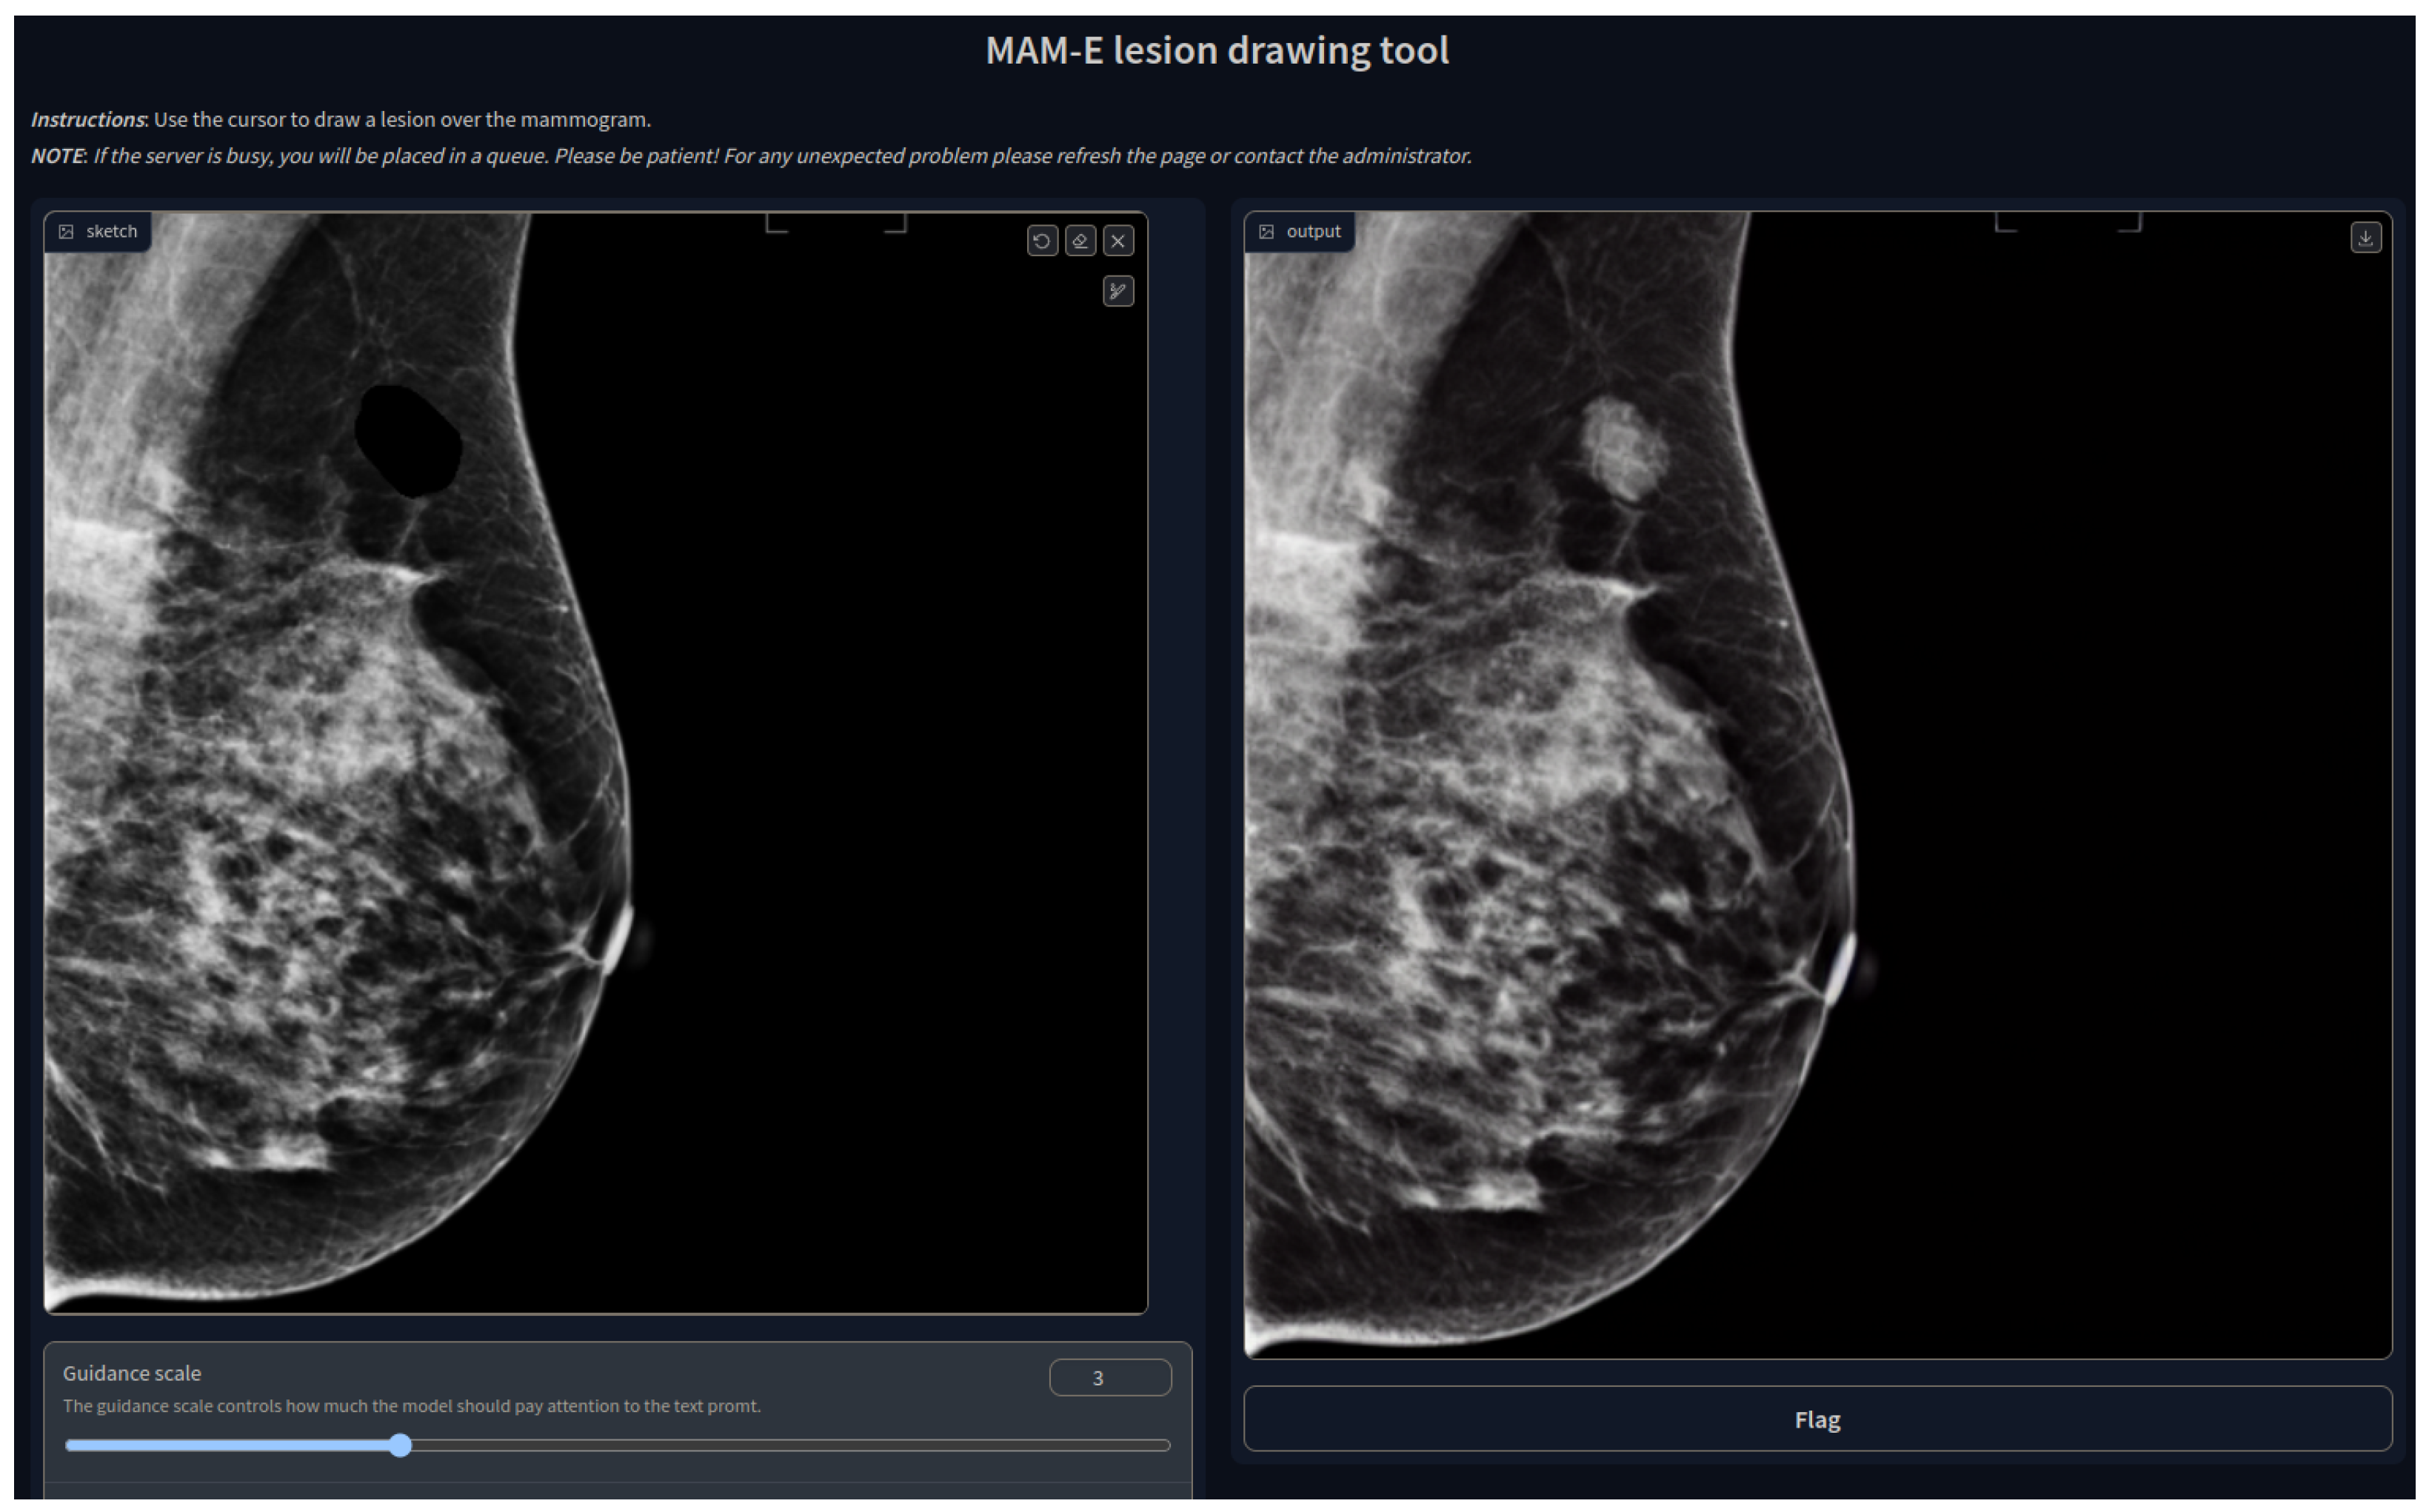

3.3. MAM-E Graphical User Interfaces